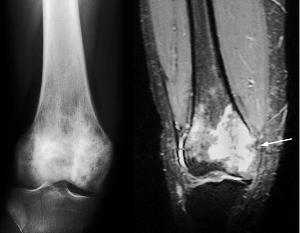

1.X线检查

原发性淋巴的X线表现多为溶性,“虫噬样”改变,在正常组织和病变组织之间有明显的分界限,部分病人有皮质的破坏和缺损,但较少有膜反应,还有部分病人表现为分离,即组织的正常部分与病变部分分离,亦可表现为病理骨折

3.MRI

骼系统的病变为破性,溶性,部分溶和部分硬化性及皮质的改变等多种表现,MRI对于原发性淋巴的诊断敏感性较高,能发现其他检查阴性的原发性淋巴,同时,它能发现周围结缔组织的病变。